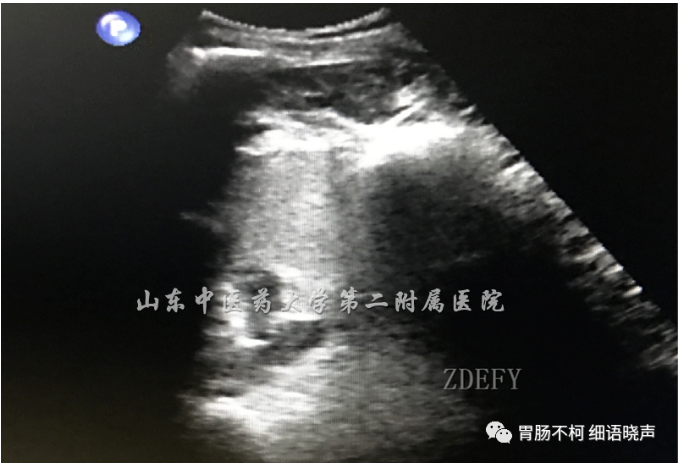

病例一:胃体大弯侧、小弯侧及前后壁见多发偏低回声、类圆形、膨胀感较强肿块

放大图像显示与腺体层关系密切